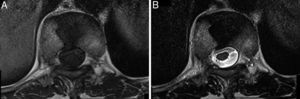

Una paciente de 62 años diagnosticada de aplastamiento vertebral osteoporótico en D10 fue remitida a un centro terciario para estudio e inicio de tratamiento antirresortivo. Refería menarquia a los 15 años y menopausia a los 45 años. Mantenía ingesta cálcica mayor a 1.000mg/día, así como exposición solar y actividad física adecuadas, y no tenía antecedentes de fracturas previas, enfermedad tiroidea o urolitiasis. Recientemente se le había diagnosticado hipercolesterolemia y recibía simvastatina, pero negaba otros fármacos. El aplastamiento vertebral se asumió como asintomático ya que no hubo dolor o traumatismo previo. A la exploración presentaba talla 147cm, peso 58kg (índice de masa corporal 26), y cifosis leve con escoliosis dorsolumbar de convexidad izquierda, pero la movilidad de columna y el examen neurológico eran normales. La analítica, incluyendo calcio, fósforo, parathormona, tirotropina, 25 (OH) vitamina D3, calciuria y reabsorción tubular de fosfato, fue normal. La densitometría era compatible con osteoporosis en columna (T score: -2,8) y cuello femoral (T score: -3,2). La radiografía lateral de columna dorsal mostraba un aparente aplastamiento vertebral anterior severo de D10, pero la resonancia magnética (RM) reveló que en realidad correspondía a una «vértebra en mariposa» típica (figs. 1 y 2). Se diagnosticó osteoporosis densitométrica y se pospuso el inicio de la terapia antirresortiva.

La vértebra en mariposa (también conocida como hendidura sagital vertebral, raquisquisis anterior, somatosquisis, o espina bífida anterior1) es una malformación congénita rara producida por el fallo de la fusión de los núcleos de condrificación laterales de la vértebra en desarrollo2,3, secundario a una regresión embriológica incompleta de la notocorda que origina un surco sagital en forma de embudo dentro del cuerpo vertebral, a través del cual se conectan los discos vertebrales adyacentes4. Este defecto ocurre entre la 3.ª a 6.ª semana de gestación2,3 y se localiza con mayor frecuencia a nivel lumbar5–7. Se asocia a otras alteraciones congénitas como la hipo/aplasia mülleriana y los síndromes de Jarcho-Levin, Pfeiffer, Crouzon, Alagille y Kallmann, aunque también puede ocurrir de forma aislada1,2,7,8. Los pacientes habitualmente son asintomáticos y esta malformación suele detectarse de forma incidental, pero puede alterar la biomecánica de la columna causando dolor lumbar atípico o aumentando la posibilidad de herniación discal5–7. En la radiografía lateral muestra una morfología trapezoidal o cuneiforme anterior, por lo que puede confundirse con un aplastamiento vertebral osteoporótico u otras fracturas vertebrales patológicas, incluyendo las traumáticas, infecciosas o metástasicas1,2,7,9. El acuñamiento es causado por hipo/aplasia anterior debido a un déficit congénito de la vascularización3,9. En la radiografía anteroposterior se detecta fácilmente debido a que la vértebra se divide en 2 hemivértebras (habitualmente simétricas, pero pueden ser de tamaño distinto condicionando escoliosis), que lucen como las alas de una mariposa1,2,4, pero esta radiografía no estuvo disponible en nuestro caso. La TC y la RM se recomiendan en casos dudosos o para excluir otras anomalías congénitas asociadas tales como barras vertebrales, vértebras lumbares supernumerarias, espina bífida, diastematomielia o cifoescoliosis6. Recientemente, se ha descrito el uso de la ultrasonografía fetal tridimensional para el diagnóstico prenatal de la vértebra en mariposa10. En conclusión, aunque la vértebra en mariposa es infrecuente, debería tenerse en cuenta en el diagnóstico diferencial del aplastamiento vertebral osteoporótico.